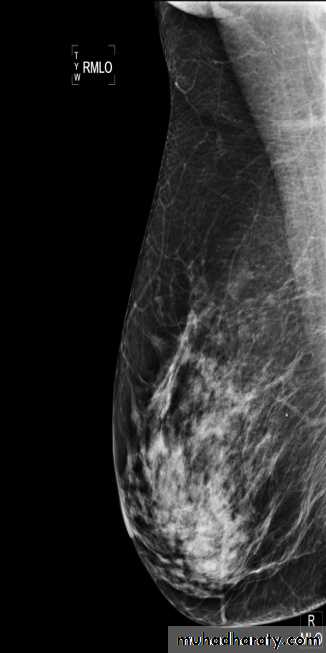

Alkindy college of medicine, university of BaghdadThe two standard views are :.

craniocaudal view (CC view)mediolateral oblique view (MLO view)

:Adequate craniocaudal views

all glandular tissue identifiednipple in profile

nipple in midline of image

images symmetric

Adequate medio-lateral oblique views

pectoral shadow seen down to level of nipple or lowerinframammary fold well seen

nipple in profile